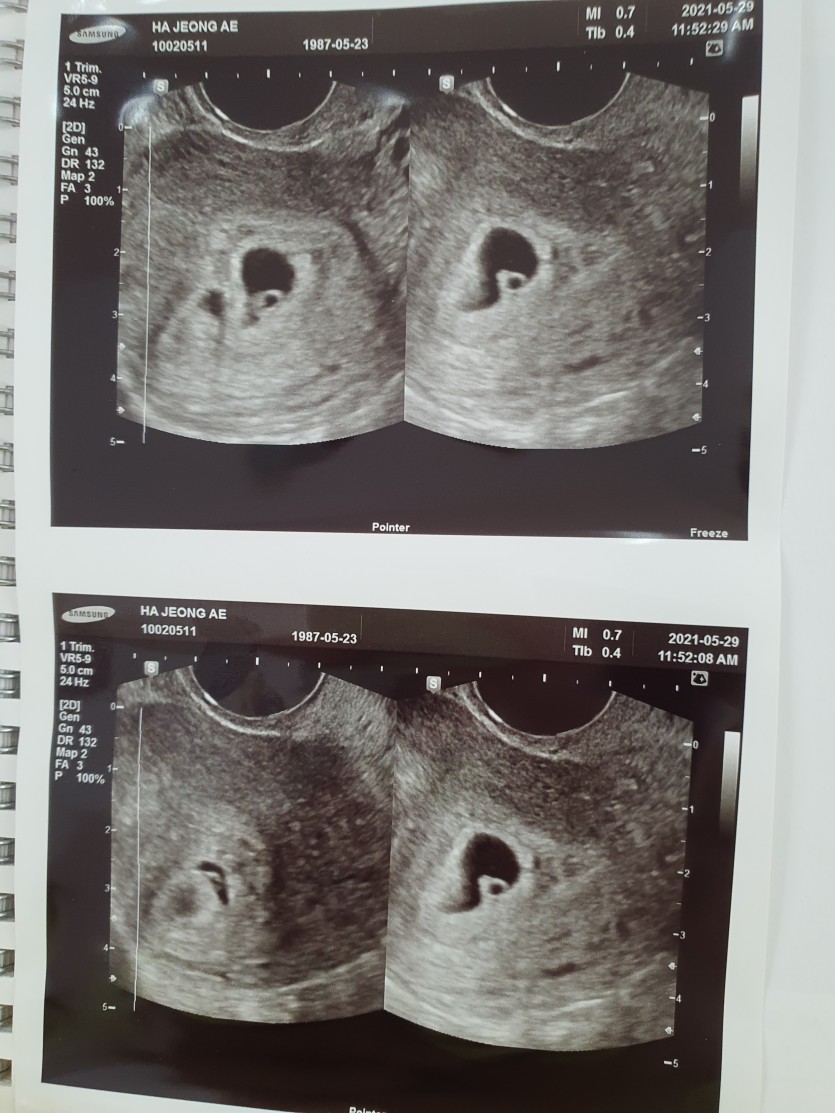

기쁨은 배로 쌍둥이가 찾아왔네요

7주가 넘어서 곧 졸업을 앞두고 있네요

셤관으로 시술하신 결과 1차에 우리 둥이들 임신 축하드립니다. 정말 기적이 일어났네요~~ㅎㅎ

사진에서는 점같이 엄청 작았지만 지금은 무럭무럭 건강하게 자라 심장이 뛰는 것도

보이고 꼬물꼬물 움직이는 것도 보이니 시간도 빠르고 신기한것 같아요 ㅎㅎ